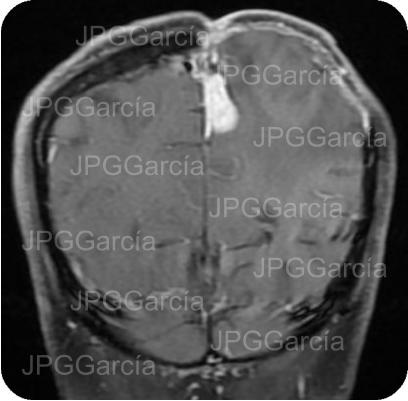

Estudio de IRM de cráneo (T2) como control postquirúrgico en donde se observa edema en la zona quirúrgica